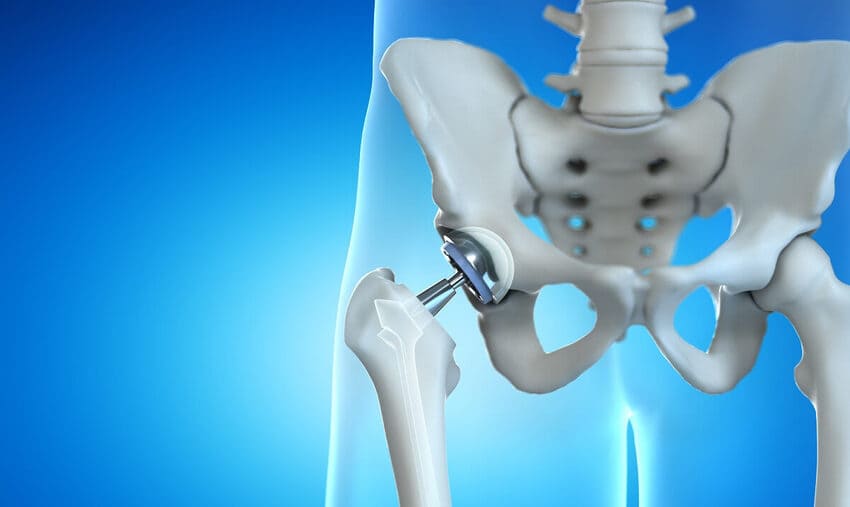

Înlocuirea totală a șoldului în Turcia la Istanbul este o procedură chirurgicală prin care cartilajul și osul bolnav din articulația șoldului sunt înlocuite chirurgical cu materiale artificiale.

În cadrul unei operații de înlocuire parțială a șoldului, cavitatea șoldului este, în general, lăsată intactă. Capul femurului este înlocuit cu o componentă artificială similară cu cea utilizată în cazul unei înlocuiri totale de șold. Uneori, un dispozitiv este plasat pe os, astfel încât partea superioară a femurului să nu fie tăiată. - Înlocuirea minim invazivă a șoldului

Implanturile artificiale se uzează în timp și poate fi necesară înlocuirea lor. Operația de revizuire a șoldului este o procedură de înlocuire a unui implant uzat.